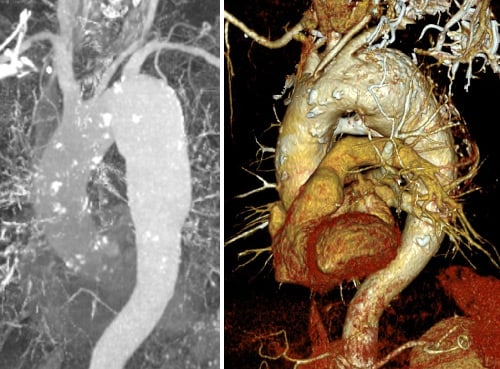

- CT scan: 66 mm aortic arch aneurysm

Complex anatomical features:

- Short brachiocephalic trunk (< 1 cm)*

- Narrow iliac vessels (5-7 mm)

- Stenosis at LCCA ostium